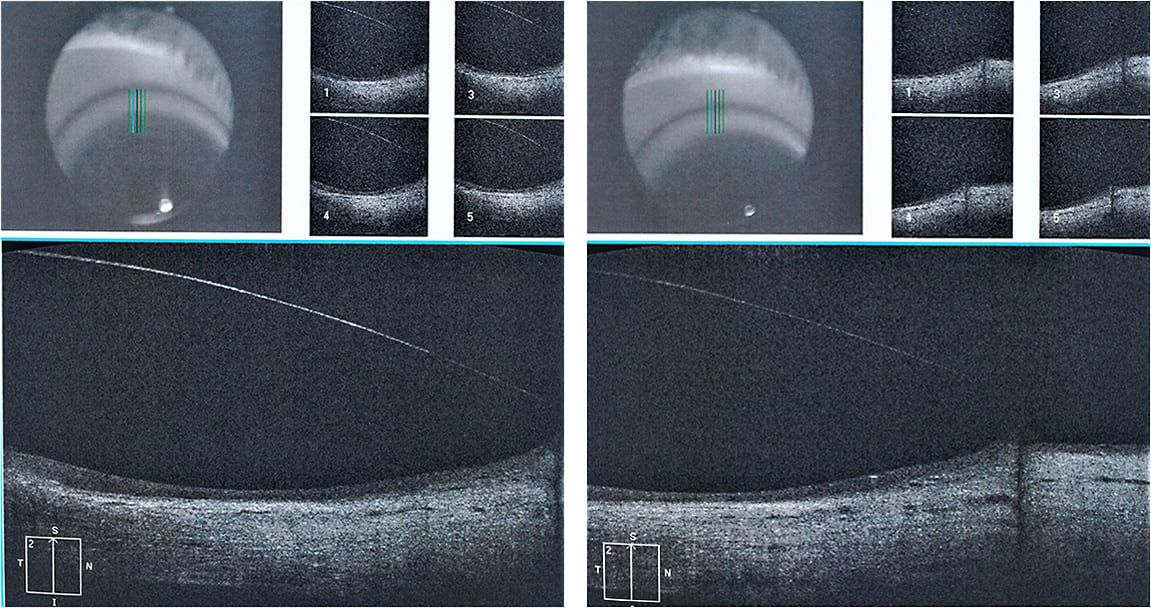

We first attempted a 17.5mm diameter scleral lens, which dropped significantly (Figure 1). It also induced debris in the liquid lens reservoir that formed within the first few minutes when the lens was still slightly loose.

The second trial lens was a 16.5mm scleral lens, which again decentered inferiorly; it decentered less than the 17.5mm lens did and it did not cause debris to enter the tear reservoir, but it was still in a low position, with a vault that was too thin at the top and too thick from the center to the bottom area of the lens.

With fluorescein, we also observed superior touch at the limbus and areas in which the haptic was loose (Figures 3 and 4). The loose and the tight areas were also evident in optical coherence tomography (OCT) images. Despite this, the patient did not complain of discomfort.